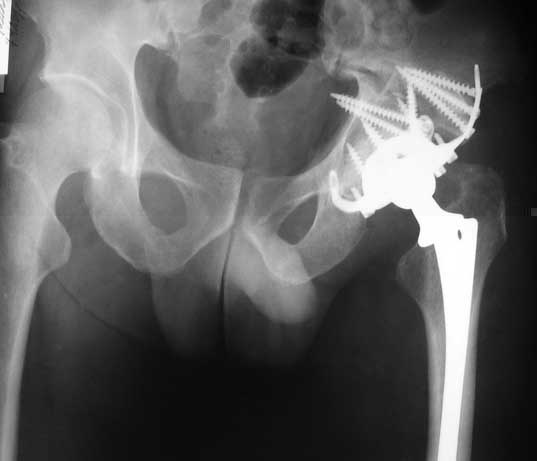

I think, if symphysis is unstable at first you must open and stabilize symphysis by plate or

external fixator or may be use both together.

Our experience showes, that reposition and stabilization pelvis in zone of old acetabular fractures with bone grafting are very traumatic and not effective due head AVN and hip arthrosis.

In such cases we use hip arthroplasty with "Octopus" acetabular system (De Puy). This system consist of acetabular ring and cementless cup.

It`s allow you to fix the reinforcement ring in proper position, then bone grafting of the defects of the acetabulum walls and floor.

Then you fix the cup to the ring.

I will show some cases.